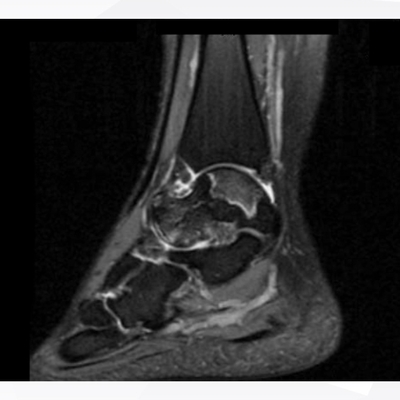

Click on an image below to view more info.